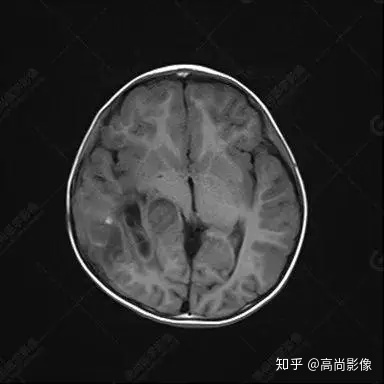

右側(cè)顳葉腫瘤切除術(shù)后(具體不詳):右側(cè)顳部骨質(zhì)不連續(xù)呈術(shù)后改變,右側(cè)顳葉術(shù)區(qū)見片狀長T1長T2信號影,F(xiàn)LAIR呈低信號;術(shù)區(qū)后方右側(cè)顳枕葉見一巨大占位性病變影,邊界欠清,大小約6.2×5.8×4.3cm(前后×左右×上下),信號不均勻,T1WI呈等稍低信號間雜少許高信號,T2WI呈高稍低混雜信號,DWI示部分病灶彌散受限,相應(yīng)ADC圖減低,磁敏感序列見部分呈極低信號,增強(qiáng)掃描可見明顯不均勻強(qiáng)化,鄰近硬腦膜及小腦幕增厚并明顯強(qiáng)化;另延髓右前方及右側(cè)橋小腦角區(qū)見一不規(guī)則形異常信號影,大小約3.2×1.3×3.7cm(左右×前后×上下),呈長T1稍長T2信號,F(xiàn)LAIR呈等信號,DWI未見受限,增強(qiáng)后明顯均勻強(qiáng)化,鄰近腦膜明顯強(qiáng)化。鄰近腦實質(zhì)及右側(cè)顳角明顯受壓;左側(cè)大腦半球未見局灶性信號異常,中線結(jié)構(gòu)稍左移。

右側(cè)顳葉腫瘤切除術(shù)后:現(xiàn)術(shù)區(qū)后方右側(cè)顳枕葉及延髓右前方占位,右側(cè)顳枕部硬腦膜及小腦幕明顯強(qiáng)化,結(jié)合既往影像資料,考慮為胚胎源性惡性腫瘤,如非典型畸胎樣/橫紋肌樣瘤(AT/RT)或原始神經(jīng)外胚層腫瘤(PNET)。

非典型畸胎樣/橫紋肌樣瘤(AT/RT) 是一種高度惡性中樞神經(jīng)系統(tǒng)腫瘤,臨床罕見,臨床表現(xiàn)無特異性,好發(fā)于 5 歲以下兒童,尤以 3 歲以下多見,在兒童原發(fā)性中樞神經(jīng)系統(tǒng)(CNS)腫瘤中占 1%~3%。該腫瘤體積一般較大,幕上大于幕下,有明顯的占位效應(yīng)。該腫瘤成分復(fù)雜,囊變、出血、壞死常見。因此 AT/RT信號混雜,囊性部分呈 T1WI低、T2WI高信號,增強(qiáng)后不強(qiáng)化;若瘤體出血,囊內(nèi)可見T1WI稍高信號、T2WI低信號,實性部分在 T1WI上呈混雜等、低信號,在T2WI 及 T2-FLAIR上呈混雜等高信號,增強(qiáng)掃描后大部分呈環(huán)形條帶樣明顯強(qiáng)化,中心壞死區(qū)不強(qiáng)化。另外,該腫瘤實性成分在DWI上呈高信號,說明腫瘤細(xì)胞核密集,水分子擴(kuò)散明顯受限,提示該腫瘤惡性程度高,容易復(fù)發(fā)及轉(zhuǎn)移。